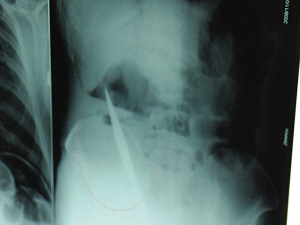

X光片上,尖刀清晰可見。

從男子體內(nèi)取出的尖刀足足有19厘米長。

6日上午,記者在徐州礦務(wù)集團總醫(yī)院重癥監(jiān)護室見到了這名男子,目前他雖然已經(jīng)恢復(fù)了意識,但還不能開口說話,需要呼吸機輔助呼吸。據(jù)醫(yī)生介紹,4日中午12時左右,這名男子因服毒輕生被緊急送到醫(yī)院進行搶救,之前,這名男子已經(jīng)在當?shù)剜l(xiāng)鎮(zhèn)醫(yī)院進行了近20小時的治療,但效果不佳!安∪吮晦D(zhuǎn)院到礦總院時已神志不清,血壓極低,處于休克狀態(tài)!本茸o人員給男子洗胃、初步處理以后,發(fā)現(xiàn)男子呼吸急促,于是趕緊給他拍片檢查。結(jié)果讓所有的醫(yī)生大吃一驚,竟有一把尖狀異物橫在該男子腹腔內(nèi)!當天下午5時30分,輕生男子被推上了手術(shù)臺。經(jīng)過40多分鐘的手術(shù),該男子腹腔被打開,手術(shù)醫(yī)生發(fā)現(xiàn),男子體內(nèi)的金屬狀異物竟然是一把長19厘米的尖刀!